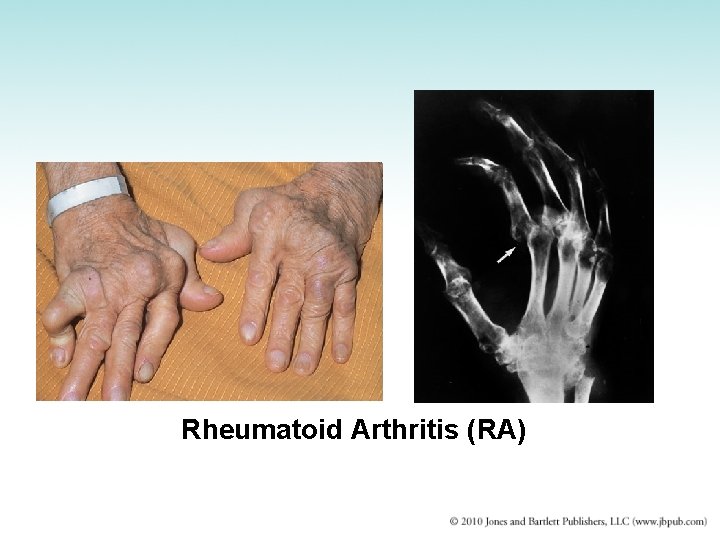

Rheumatoid Arthritis (RA) • Systemic disease affecting connective tissues throughout the body, specially the joints • Produces chronic inflammation and thickening of synovial membrane • Classified as an autoimmune disease • Rheumatoid factor: autoantibody in blood and synovial tissues; produced by B lymphocytes directed against individual’s own gamma globulin • Encountered most frequently in young men and middle-aged women • Usually affects small joints of hands and feet • Dislocation from joint instability

Rheumatoid Arthritis (RA)

Rheumatoid Arthritis (RA)